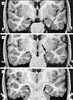

Mesial temporal sclerosis

Hippocampal sclerosis (HS) is a neuropathological condition with severe neuronal cell loss and gliosis in the hippocampus, specifically in the CA-1 (Cornu Ammonis area 1) and subiculum of the hippocampus. It was first described in 1880 by Wilhelm Sommer. [Source: Wikipedia ]